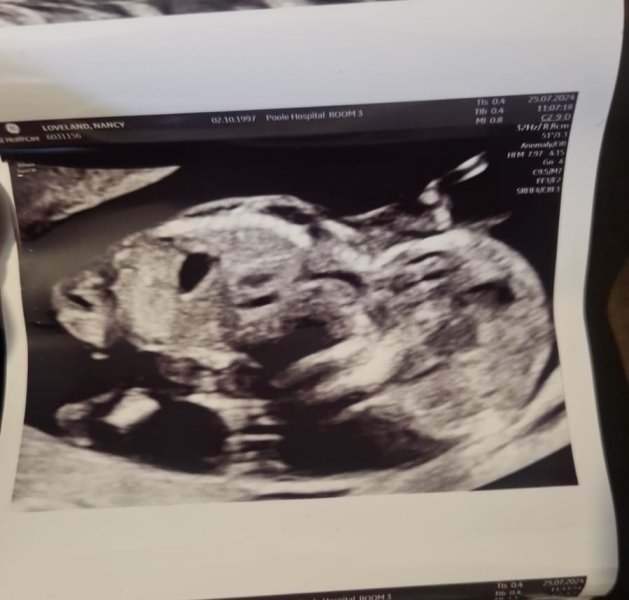

Does anyone kno how to work it out or if they even can with this scan photo lol? I’m 13 weeks 3 days

You might want to remove your personal details from the picture